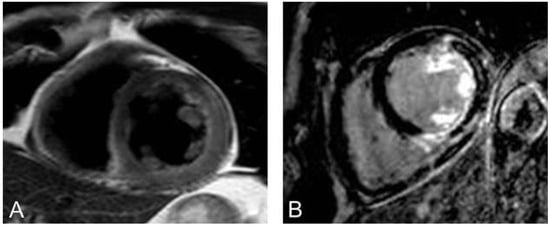

Figure 2. (A,B) zeigen die typischen 3 Kurzachsenorientierungen des linken Ventrikels, die während einer Perfusionsuntersuchung aufgenommen werden. (A) zeigt eine belastungsinduzierte Perfusionsstörung in der lateralen linksventrikulären Wand. (B) Unter Ruhebedingungen liegt keine Perfusionsstörung vor. C zeigt viables Myokard in den Late-gadolinium-enhancement-Aufnahmen auch in den Myokardsegmenten, die unter Belastung eine Perfusionsstörung aufweisen. Es liegt eine belastungsinduzierte Isch ämie vor.

Myokardiale Perfusionsuntersuchung

Die Herz-MRI-Perfusionsuntersuchung beruht auf der Darstellung der Passage eines gadoliniumhaltigen Kontrastmittels während der Hyperämiereaktion, die durch einen pharmakologischen Vasodilatator erzielt wird. Da Gadolinium ein positives Kontrastmittel ist (hell in T1-gewichteten Aufnahmen), stellt sich normal perfundiertes Myokard während der pharmakologisch induzierten Hyperämie hell in T1-gewichteten Aufnahmen dar. Myokardsegmente, die unter pharmakologischer Hyperämie nicht oder verzögert perfundiert werden, kommen dunkel zur Darstellung (Figure 2A). Um die Anzahl falsch-positiver Befunde aufgrund von Arte fakten zu minimieren, kann eine Ruheperfusion angeschlossen werden (Figure 2B). Die Kontrastmitteldosis beträgt zwischen 0,05 und 0,1 mmol/kg Körpergewicht. Üblicherweise kommt als Vasodilatator Adenosin zum Einsatz, das intravenös über mindestens 3 Minuten verabreicht wird. Adenosin hat eine kurze Halbwertszeit (ca. 12 Sekunden) und ist eine sichere Substanz für die klinische Verwendung [16]. Als wichtigste Kontraindikationen sind allergisches Asthma bronchiale, schwere obstruktive Lungenerkrankungen und höhergradige AV-Blockierungen zu nennen, als weitere Kontraindikationen sind Sinusknotendysfunktionen und schwere Hypo- oder Hypertonie aufzuführen. Seltene Nebenwirkungen sind Bronchospasmus und eine transiente AV-Knotenblockierung. Mittlerweile gibt es alternative Substanzen, wie den selektiven A2a-spezifischen Adenosinrezeptoragonisten Regadenoson, der in Europa verfügbar ist und ein geringeres Neben wirkungsspektrum aufweist [17,18]. Die überwiegende Anzahl klinischer Studien wurde bei Feldstärken von 1,5 Tesla durchgeführt, so dass die grösste Evidenz hierauf beruht. Neuere vergleichende Studien zur Diagnostik relevanter Koronarstenosen zeigen eine Überlegenheit der Perfusionsuntersuchung bei einer Feldstärke von 3 Tesla [19,20]. Die Aufnahmesequenz sollte T1-gewichtet und EKG-getriggert sein [21]. Die Perfusionsaufnahme dauert ca. 10 Sekunden und wird unter Atemanhalt durchgeführt, um Bewegungsartefakte möglichst gering zu halten [22]. In der Regel werden drei Schichten (basal, midventrikulär und apikal) des linken Ventrikels in axialer Orientierung aufgenommen. Neuere Verfahren erlauben mittlerweile auch die dreidimensionale (3D-)Erfassung myokardialer Perfusion und somit auch die Bestimmung des prozentualen Anteils ischämischen Myokards [15,23–25]. In der klinischen Routine wird die Perfusion visuell analysiert. Bei speziellen Fragestellungen oder wissenschaftlichen Untersuchungen kann eine quantitative, automatisierte Auswertung durchgeführt werden.

Viables Myokard und Narbengewebe